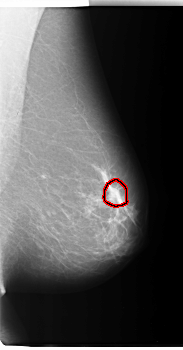

FILE: C_0040_1.LEFT_MLO.OVERLAY

TOTAL_ABNORMALITIES 1

ABNORMALITY 1

LESION_TYPE MASS SHAPE LOBULATED MARGINS OBSCURED

ASSESSMENT 3

SUBTLETY 3

PATHOLOGY MALIGNANT

TOTAL_OUTLINES 1

BOUNDARY